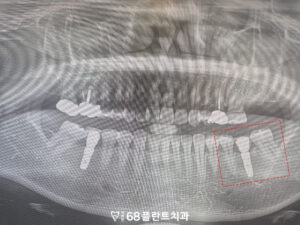

철산역치과 철산역치과

오른쪽 위를 포함하여

양쪽 아래 치아들에서도

치아에 금이 간 상태가

확인되는 상황이었습니다.

또한 기존에 식립되어 있던

임플란트 역시 사용 기간이

상당히 지난 상태로,

보철물과 주변 상태에 대한

확인이 필요한 상황이었는데요.